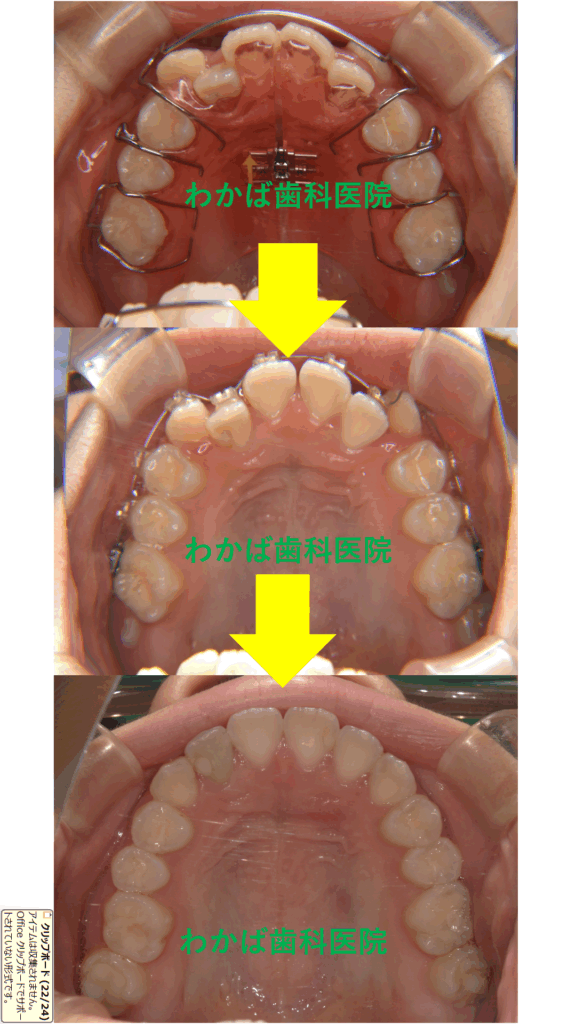

高校1年生の症例です🔍

小学5年生から矯正をスタートしました❣️

上下とも拡大床1個+下サンド1個+上ブラケット装着+リテーナーを使用しました。